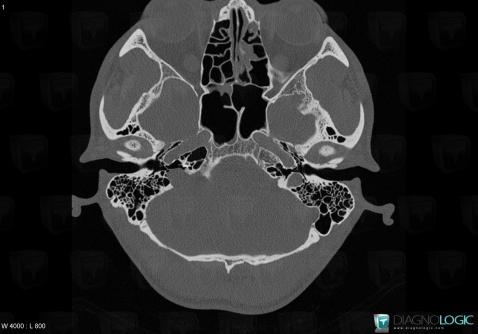

Schwannome, Espaces profonds de-face, Scanner

Voici les informations spécifiques à l'image clé ci dessus:

- Diagnostic Schwannome, Localisation(s) Espaces profonds de la face, comportant les gammes Lésion de l'espace carotidien, Masse solide cervicale